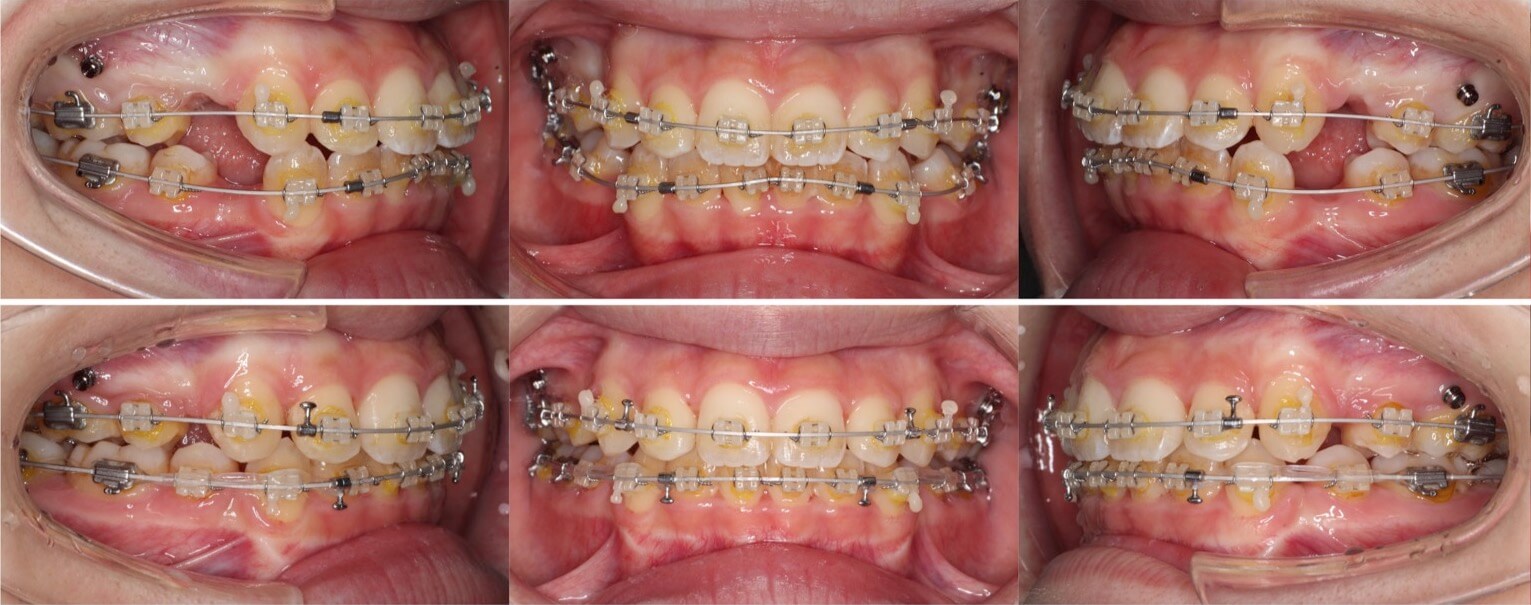

「前歯の角度が変化」

20代女性・ハーフリンガル装置・下あご後退型

前歯が前に傾斜している(倒れている)上下顎前突症例です。抜歯スペースに前歯を押し込むだけで、口元の突出が改善できる割と単純なケースになります。治療後は上下の前歯の角度も内向きに変わりました。

<症例概要>

主訴:前歯を引っ込めたい

年齢・性別:20代女性

住まい:千葉県佐倉市

症状:下顎後退・上下顎前歯唇側傾斜

治療方針:抜歯空隙の閉鎖(最大固定)

治療装置:ハーフリンガル矯正装置(上のみ裏側装置)

固定:歯科矯正用アンカースクリュー(口蓋側壁x2)

抜歯:上下第一小臼歯

治療期間:1年10か月

リテーナー:上下プレートタイプ+クリアタタイプ+フィックスタイプ

治療費用:1,4950,000(税込)

代表的副作用:痛み・治療後の後戻り・歯根吸収・歯髄壊死・歯肉退縮

▶︎その他の副作用